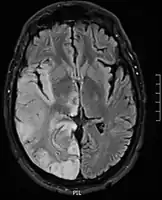

![]() Postcontrast FLAIR of a case of meningitis. It shows enhancement of meninges at the tentorium and in the parietal region, with evidence of dilated ventricles. |